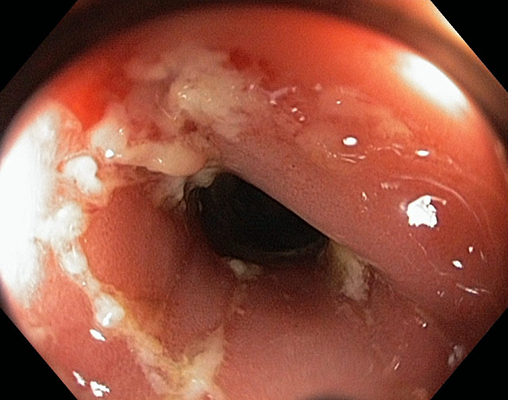

肛门癌的症状表现有哪些

肛门癌早期症状主要包括以下方面1 肛门瘙痒肿瘤可能刺激肛门周围神经末梢,引发持续性或间歇性瘙痒,尤其在夜间或潮湿环境下加重此症状易被误认为普通皮炎或痔疮,需结合其他表现综合判断2 肛门出血排便时可能出现鲜红色血液,量...